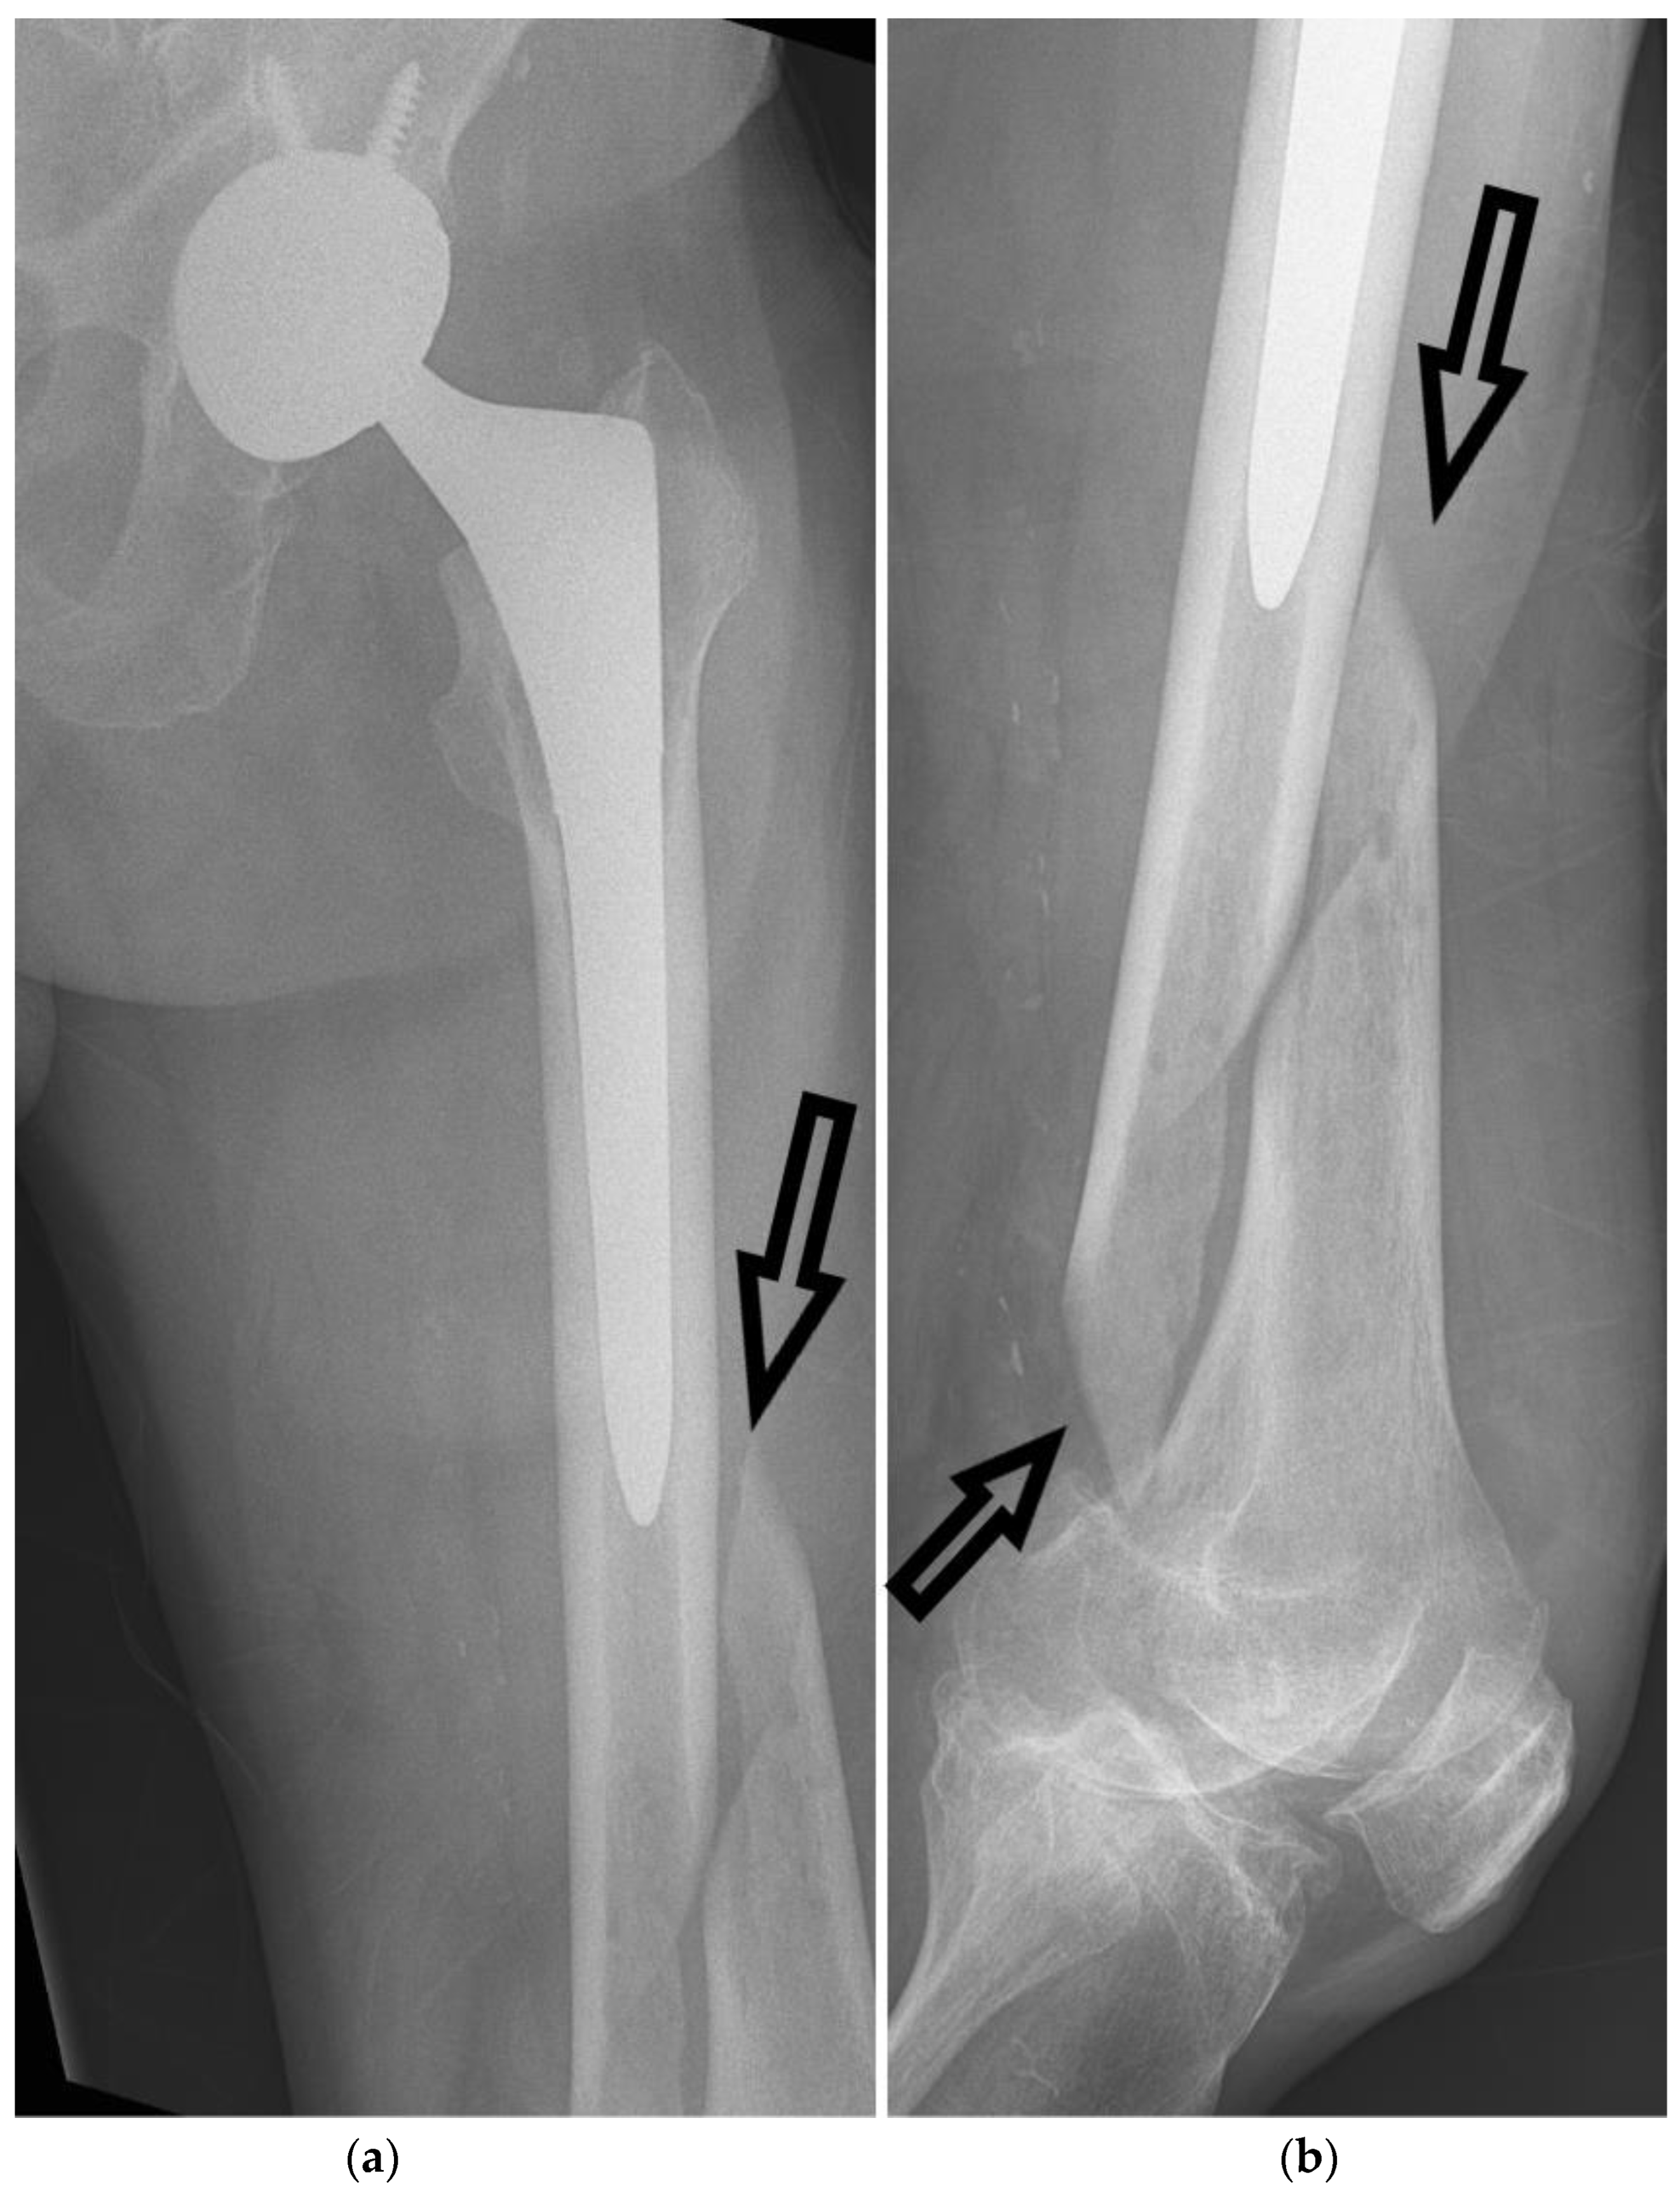

From www.mdpi.com

Anatomia Free FullText Radiological Diagnosis and Imaging of How Painful Is A Spiral Fracture The type of pain depends on the severity of the injury. Treatment can depend on the severity of the. a spiral fracture is a bone fracture that occurs when a long bone is broken by a twisting force. Spiral fractures can cause a variety of symptoms, which may vary depending on the location. the most common and obvious. How Painful Is A Spiral Fracture.

Anatomia Free FullText Radiological Diagnosis and Imaging of How Painful Is A Spiral Fracture Spiral fractures can cause a variety of symptoms, which may vary depending on the location. symptoms of spiral fractures. a spiral fracture is a bone fracture that occurs when a long bone is broken by a twisting force. the most common and obvious symptom of a spiral fracture is pain in the injured area. The pain can. How Painful Is A Spiral Fracture.

From www.bonefractures.org

Spiral fracture tibia fixed with intamedullary nail How Painful Is A Spiral Fracture spiral fractures can be more complicated regarding treatment and healing than other fractures. typical symptoms of a spiral fracture include severe pain at the fracture site, swelling, tenderness, bruising or. spiral fractures usually result in intense pain, accompanied by several common symptoms that include: Spiral fractures create a jagged edge around the bone, while other fractures—such as. How Painful Is A Spiral Fracture.

Spiral fracture tibia fixed with intamedullary nail How Painful Is A Spiral Fracture Spiral fractures can cause a variety of symptoms, which may vary depending on the location. The pain can be sharp or dull, depending on the severity of the break. typical symptoms of a spiral fracture include severe pain at the fracture site, swelling, tenderness, bruising or. Treatment can depend on the severity of the. a spiral fracture is. How Painful Is A Spiral Fracture.

Spiral fracture tibia fixed with intamedullary nail How Painful Is A Spiral Fracture Spiral fractures create a jagged edge around the bone, while other fractures—such as a transverse or oblique fracture—break in a straight line (also called a clean break). The pain can be sharp or dull, depending on the severity of the break. Spiral fractures can cause a variety of symptoms, which may vary depending on the location. typical symptoms of. How Painful Is A Spiral Fracture.